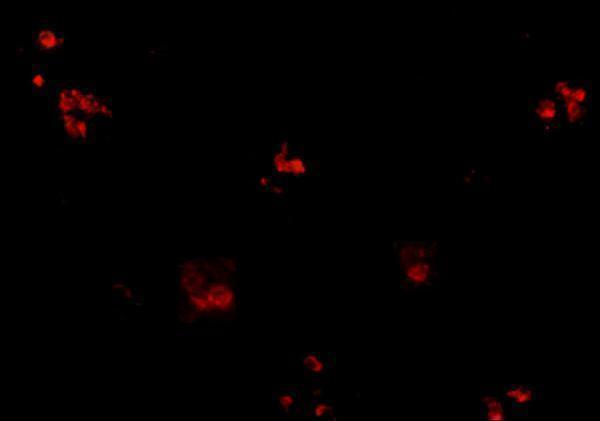

Facts about BTB/POZ domain-containing protein KCTD15.

| Gene Name: | KCTD15 |

| Uniprot: | Q96SI1 |

| Entrez: | 79047 |

BTB/POZ domain-containing protein KCTD15; MGC25497; MGC2628; potassium channel tetramerisation domain containing 15

PMID: 23382213 by Zarelli V.E., et al. Inhibition of neural crest formation by Kctd15 involves regulation of transcription factor AP-2.